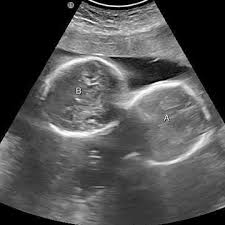

अल्ट्रासाउंड जांच में महिला के गर्भ में दो बच्चों की पुष्टि हुई थी

इंदौर। इंदौर के ESIC अस्पताल से प्रेगनेंसी का एक बेहद चौंकाने वाला मामला सामने आया है. यहां पर एक महिला ने तीन बच्चों को जन्म दिया. इससे भी ज्यादा हैरान कर देने वाली ये है कि जब डॉक्टर ने डिलीवरी से पहले अल्ट्रासाउंड किया था तब रिपोर्ट में दो बच्चे ही दिख रहे थे. लेकिन जब महिला ने तीन बच्चों को जन्म दिया तो डॉक्टर भी हैरान रह गए।